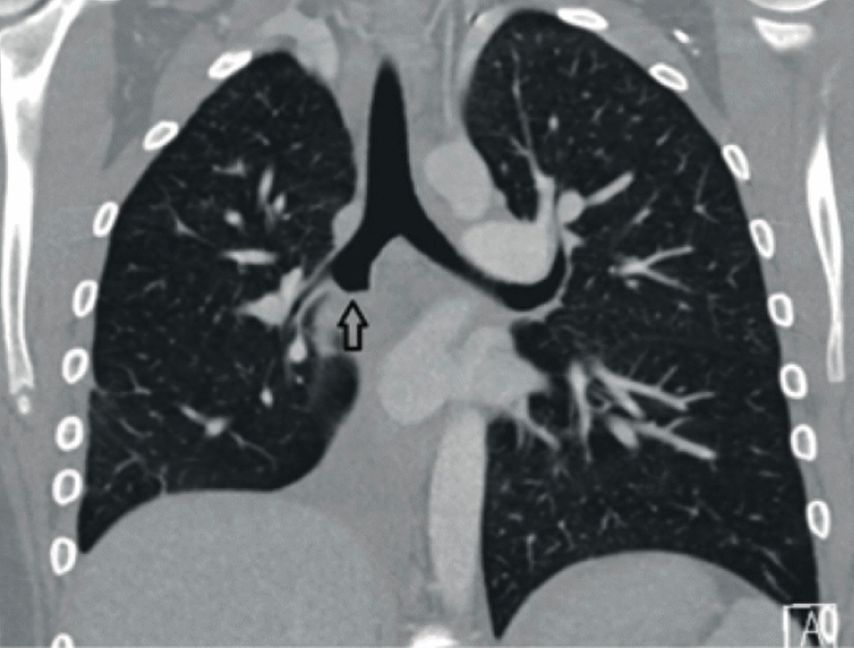

Bei der aktuellen Vorstellung wurde eine intravenöse antibiotische Behandlung initiiert, daraufhin sistierten die Hämoptysen. Thoraxsonografisch zeigte sich aber eine Persistenz der Unterlappenatelektase. In der daraufhin durchgeführten CT-Thoraxaufnahme ergab sich der Verdacht auf einen Komplettverschluss des distalen Anteils des rechten Bronchus intermedius (Abb. 2). Zur weiteren Abklärung des Befunds wurde eine flexible Bronchoskopie durchgeführt, hier zeigte sich der Befund einer endobronchialen Raumforderung (Abb. 3) mit Komplettverlegung des Bronchus, zudem waren in der endobronchialen Ultraschalluntersuchung (EBUS) suspekte Lymphknoten zu erkennen. In der gleichen Sitzung wurden aus Tumor und Lymphknoten Biopsien entnommen.

Abb. 2: a: CT-Thorax, Transversalschnitt, Tumor mit Pfeil markiert, b: CT-Thorax, Frontalschnitt, Tumor mit Pfeil markiert (rechte Lunge)